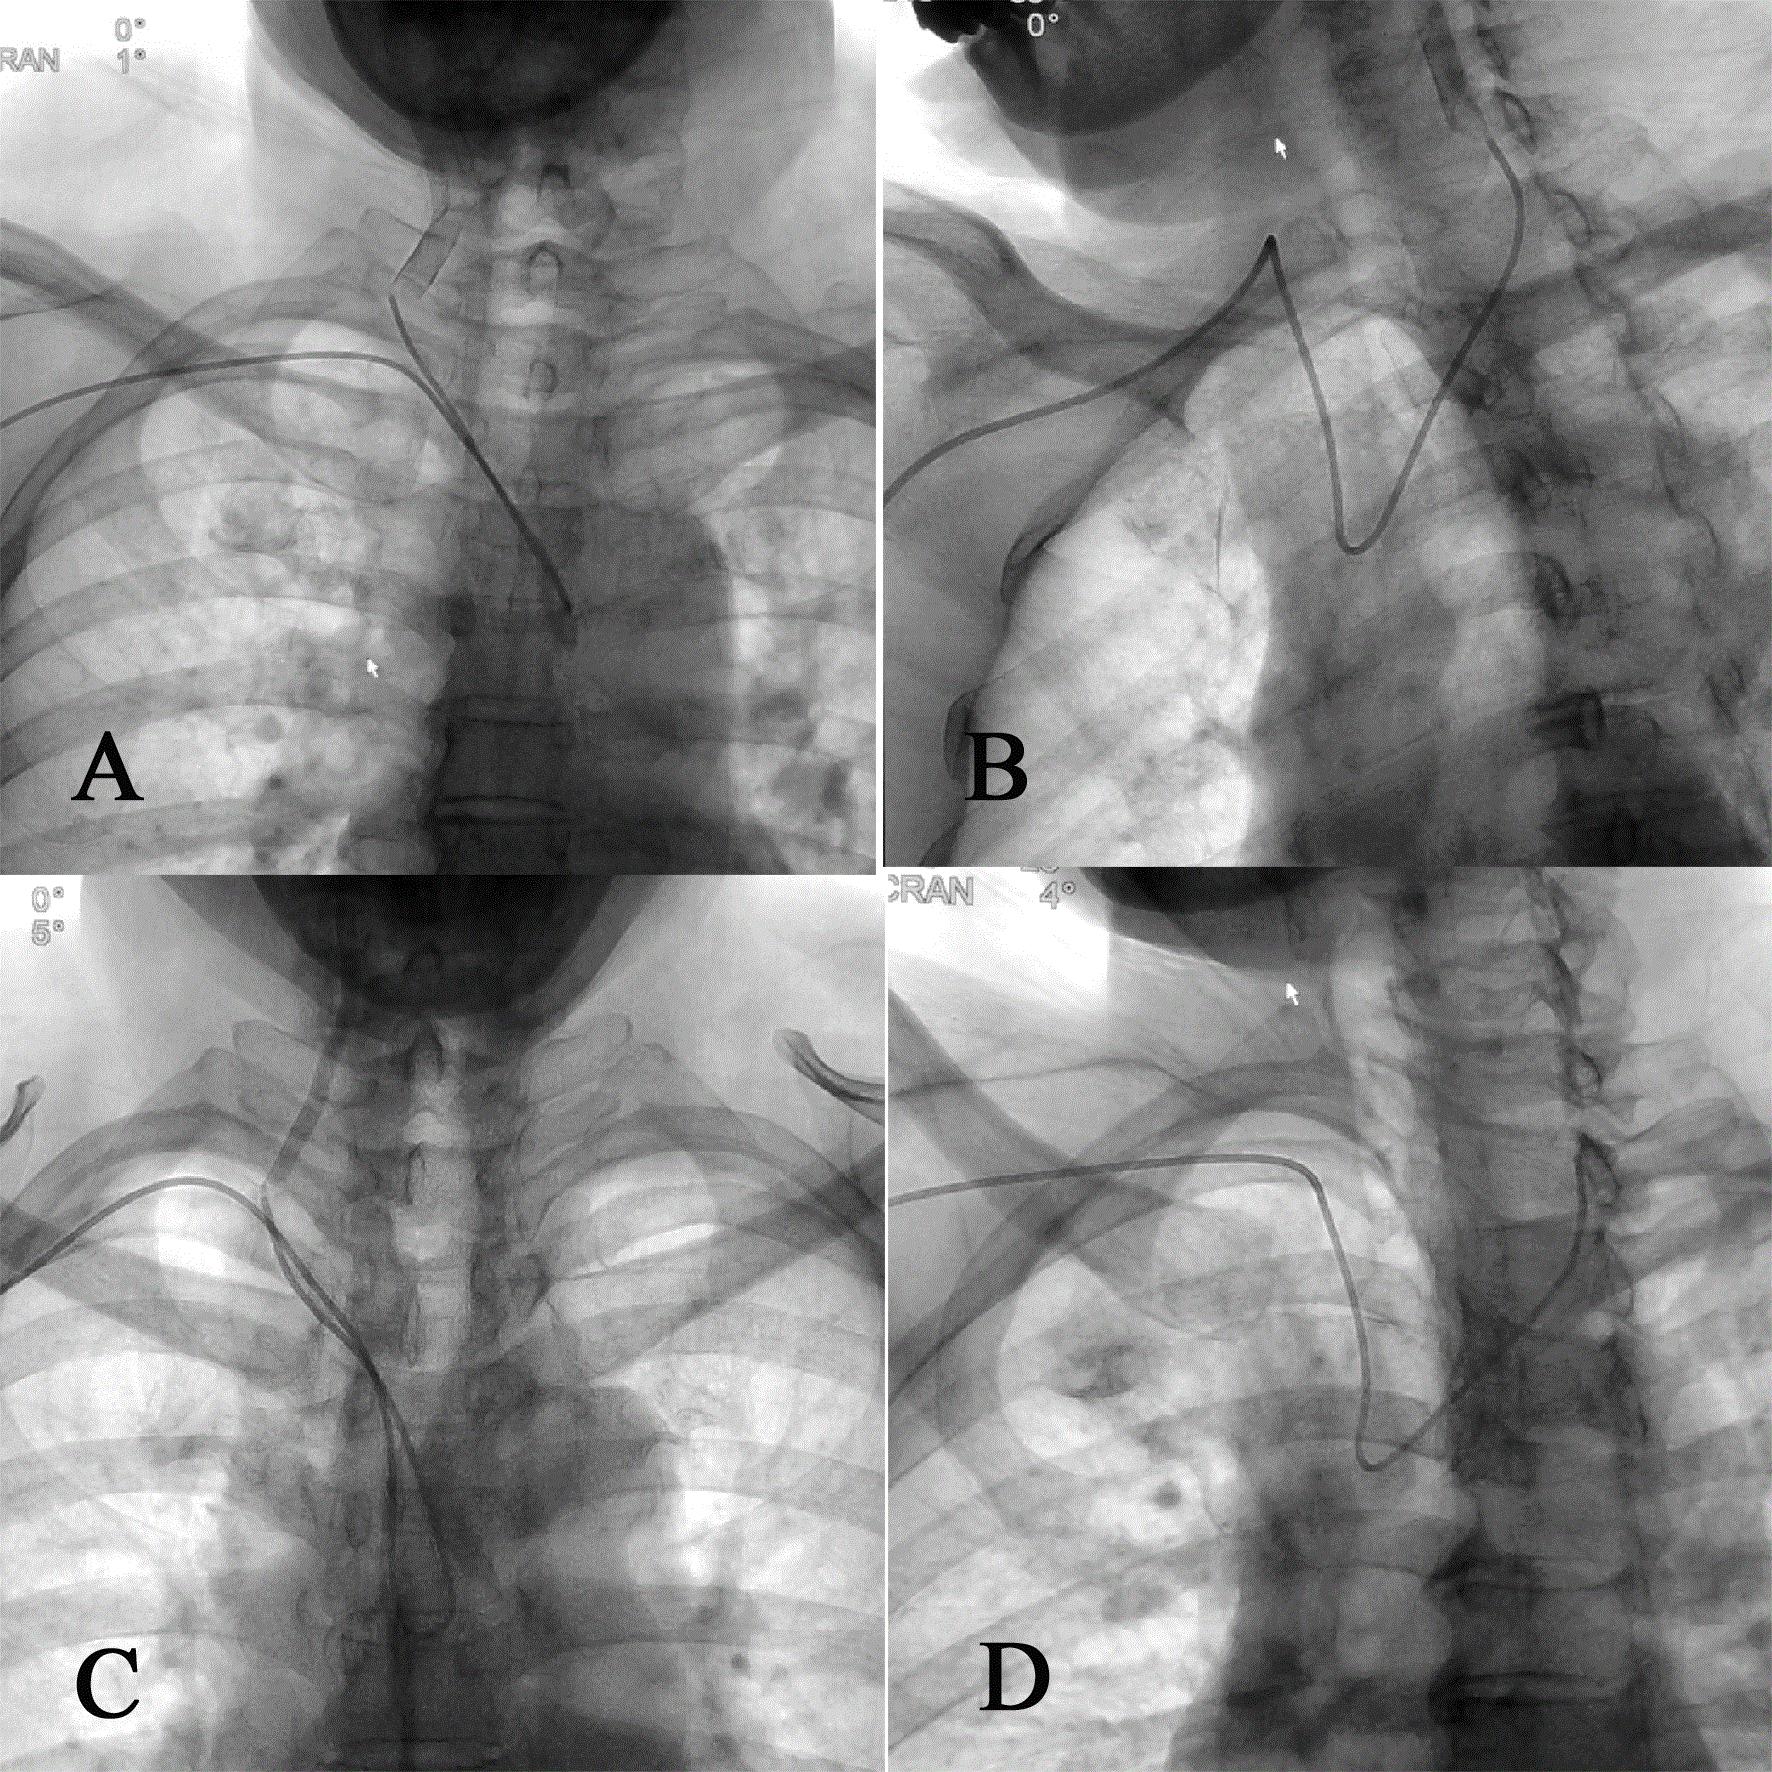

改良导管分别对左、右侧颈总动脉及左、右侧椎动脉的超选示意图。